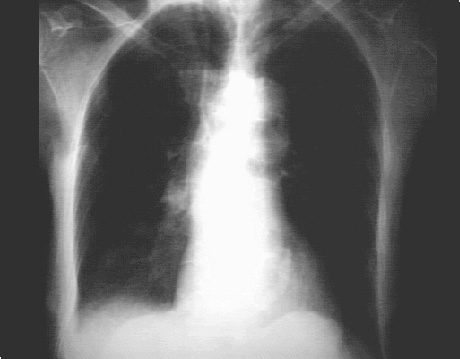

You are incorrect - our patient's chest X rays show left atrial enlargement and right ventricular enlargement.

In this overpenetrated PA view, it is demonstrated by the curvilinear density adjacent to the thoracic spine and within the cardiovascular silhouette.